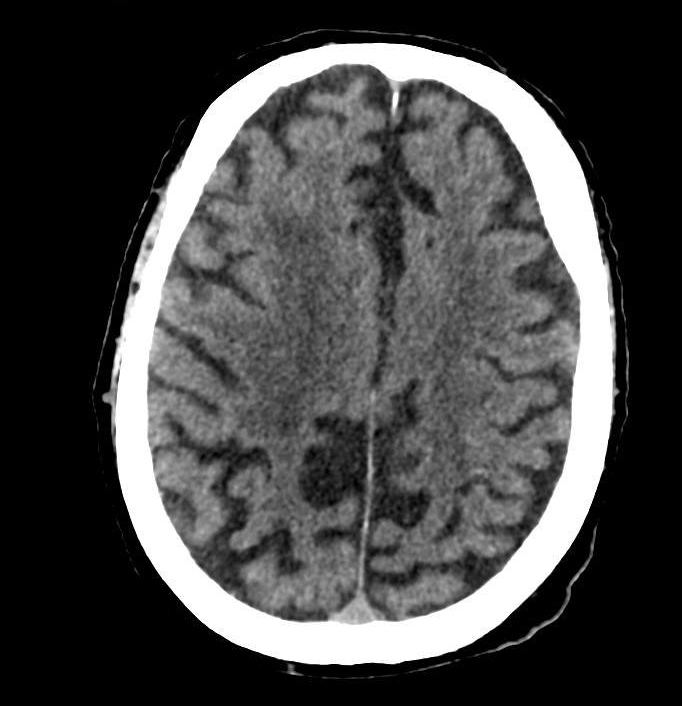

Il s’agit de céphalées matinales d’évolution progressive depuis un mois devant faire évoquer une hypertension intracrânienne et toutes ses causes (y compris une thrombose veineuse cérébrale), une méningite chronique, une hypertension artérielle incontrôlée, ou une artérite a cellules géantes.